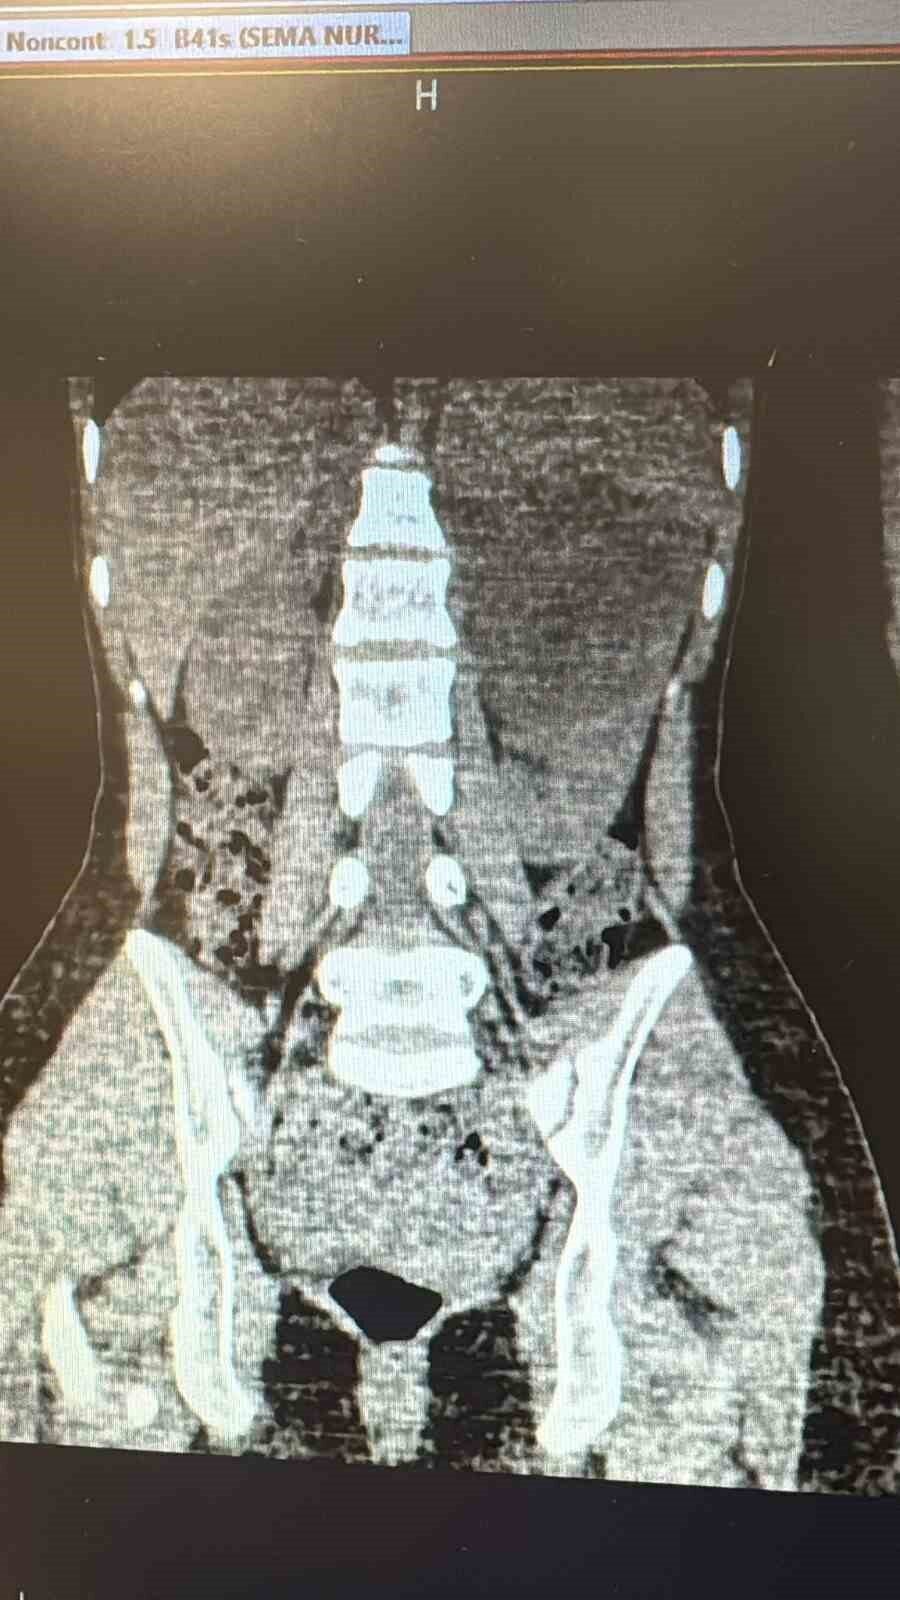

Şanlıurfa Viranşehir Devlet Hastanesi’nde, 18 yaşındaki bir hastanın sol böbreğinde tespit edilen yaklaşık 10 santimetre çapındaki kist, laparoskopik (kapalı) yöntemle başarıyla çıkarıldı.

Uzun süredir sol yan ağrısı şikâyeti çeken kadın hasta, dış merkezde yapılan tetkiklerde sol böbrekten kaynaklanan, böbrek ve dalağı iterek komşu organlara yapışıklık gösteren büyük bir kistin varlığının tespit edilmesi üzerine Viranşehir Devlet Hastanesi’ne sevk edildi. Hastanede yapılan değerlendirmeler sonucunda kistin cerrahisi için karar alındı.